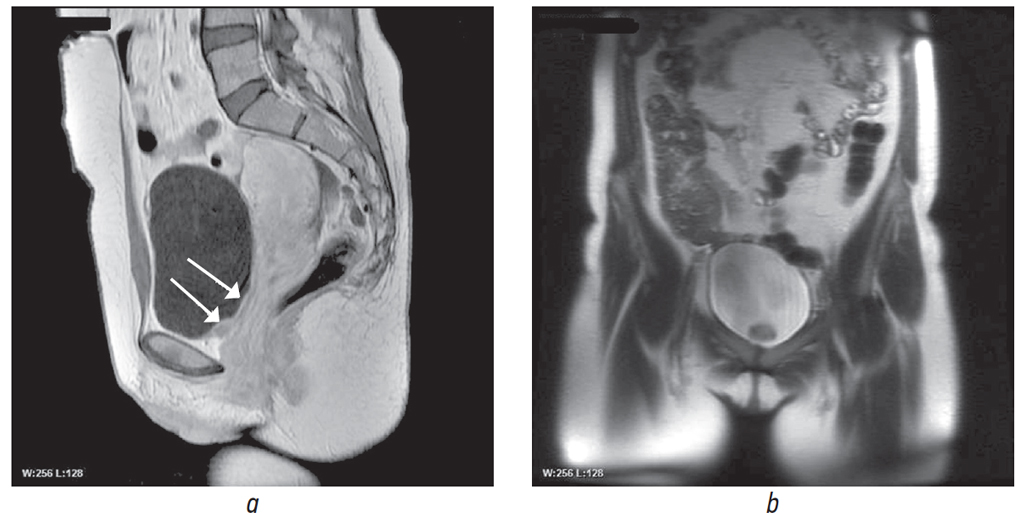

По результатам МРТ малого таза с контрастным усилением патологических изменений мочевого пузыря не выявлено. Но при последующем более тщательном изучении томограмм удалось обнаружить утолщение стенок мочевого пузыря, особенно задней и в области дна мочевого пузыря, максимально до 2 см (рис. 1).

Рис. 1. Магнитно-резонансная томография органов малого таза с внутривенным контрастированием: а — саггитальная проекция; b — аксиальная проекция. Стрелками указаны утолщения стенки мочевого пузыря

Fig. 1. Contrast-enhanced magnetic resonance image of the pelvis: а – sagittal projection; b – axial projection. The arrows indicate the thickening of the bladder wall